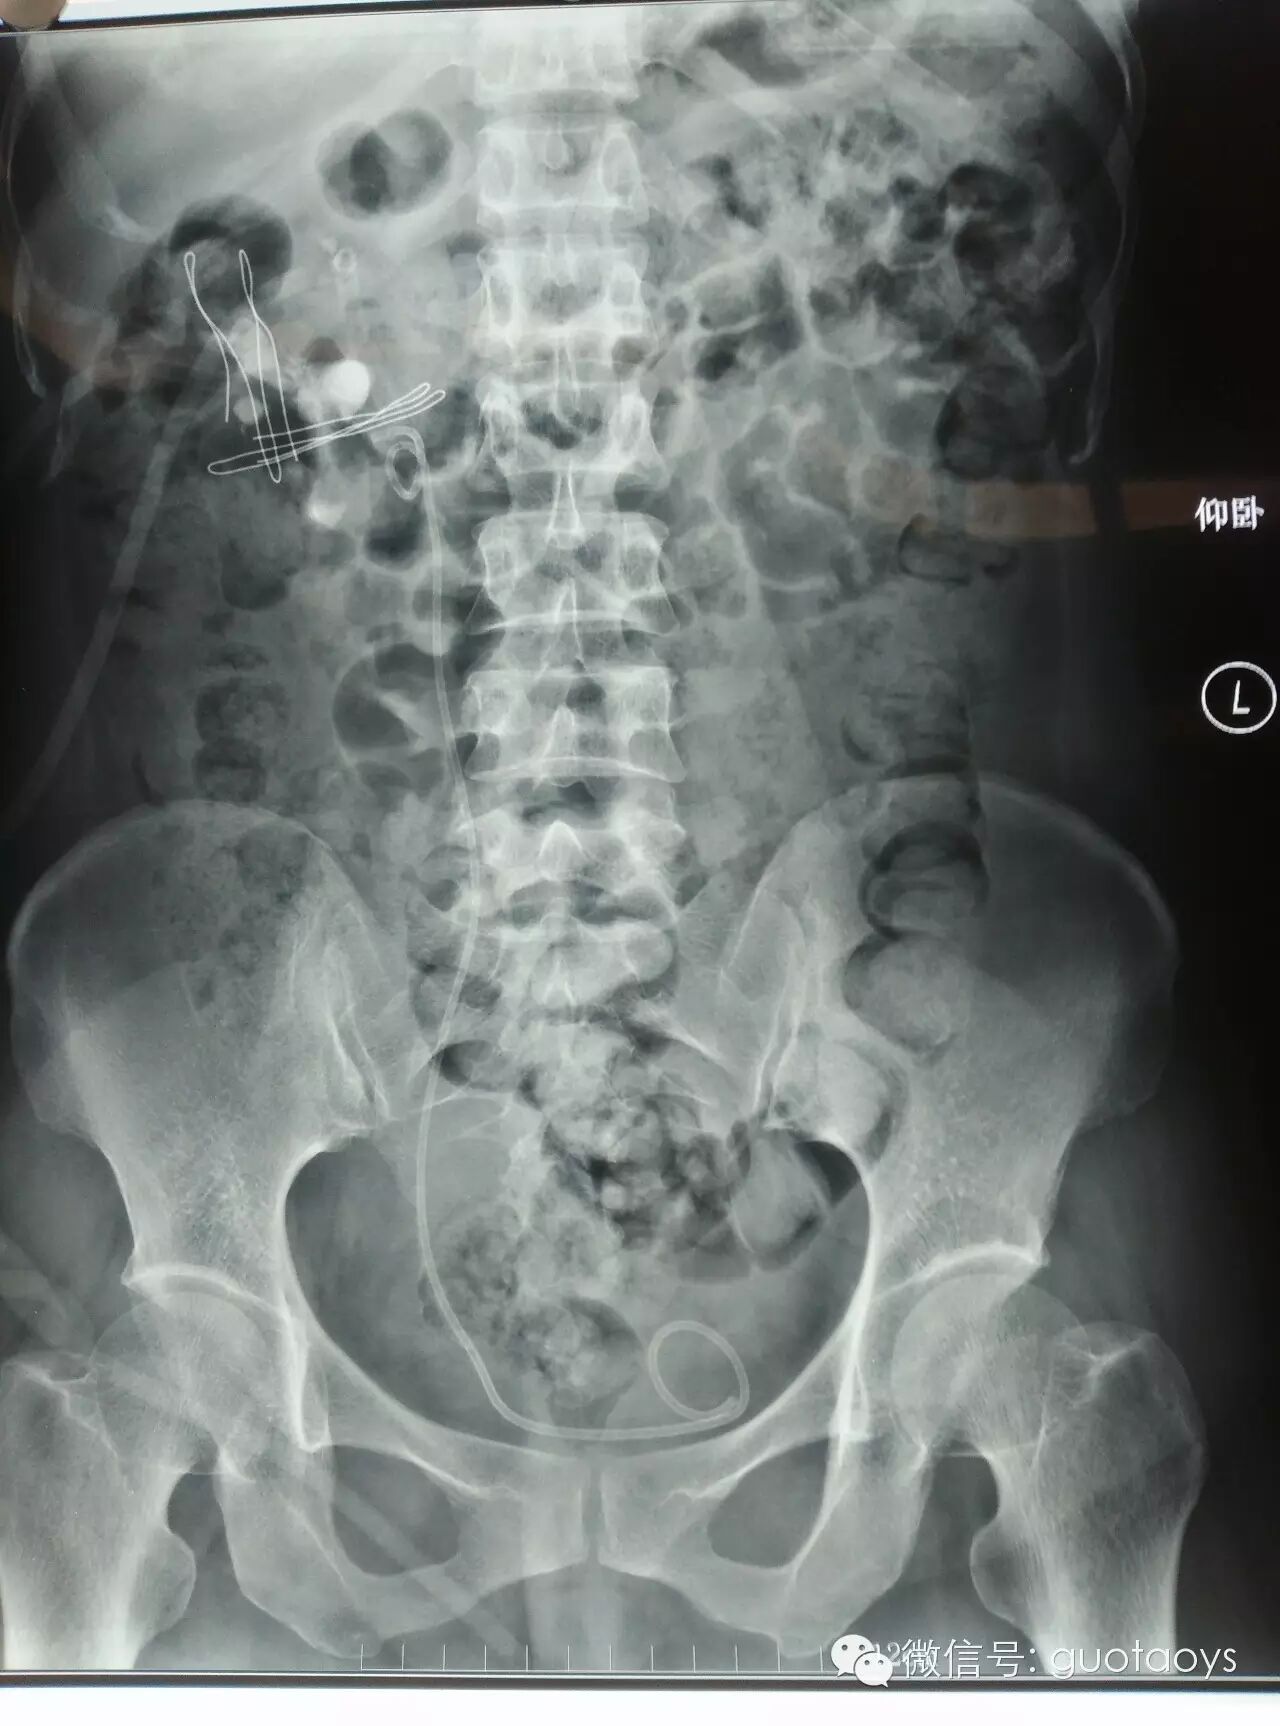

术前KUB